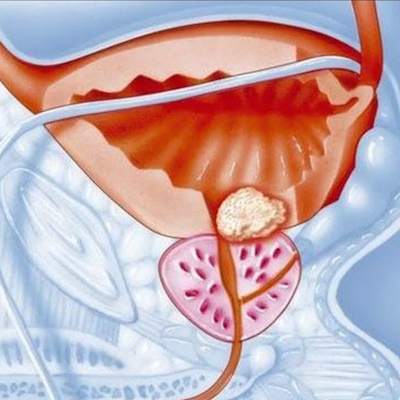

Příznaky rakoviny prostaty se v raných stadiích obvykle neprojevují. Kromě adenokarcinomu mají lidé se zvýšeným rizikem vzniku karcinomu prostaty téměř vždy souběžné patologické stavy (zánět prostaty, adenom prostaty) a ty mohou vyvolat příznaky.

Základem screeningu a diagnostiky karcinomu prostaty je biopsie prostaty, jinými slovy morfologické ověření.

Nejčastěji se rakovina slinivky břišní zjistí při preventivní prohlídce prostaty (doporučuje se všem mužům starším 40 let).

Aby bylo možné onemocnění včas rozpoznat a zahájit léčbu, je nutná prevence rakoviny prostaty, která spočívá v pravidelných lékařských prohlídkách.

Lékařská centra také pomáhají předcházet rakovině prostaty tím, že pacientům nabízejí pravidelný preventivní screening, tj. rychlé a přesné vyšetření prostaty na patologické změny.